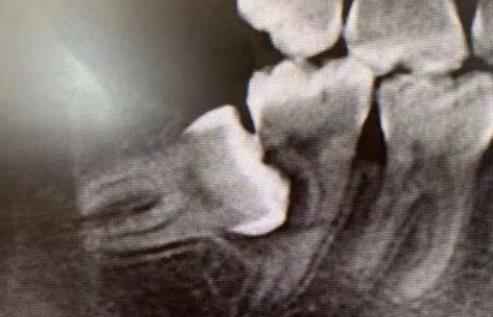

智齒造成鄰牙齲壞

如果是智齒本身齲壞或者是位置不正造成鄰牙齲壞,經常發炎腫痛,沒有對頜牙等,大部分醫生都會(hui) 建議拔除智齒的。

還有很少的情況會(hui) 有智齒位置端正,方向正常,而且有對頜牙,沒有出現其他異常的話,是可以暫時保留的,還有如果是智齒完全埋伏在牙槽骨內(nei) ,不會(hui) 對前牙和對頜牙造成影響的,也可以暫時不用管。